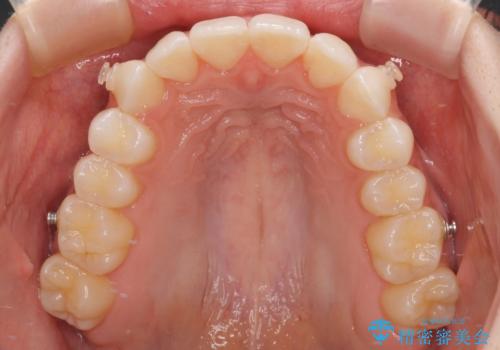

前歯のデコボコと深い咬み合わせ インビザラインできれいに改善

- インビザライン

- 11ヶ月

インビザラインによる上下歯列の拡大と、IPR(歯と歯の間を削る)にるスペースの獲得により、口元のデコボコとディープバイトを改善することとしました。

インビザラインは、装着していない時間がどれだけ短いかが、治療期間を大きく左右します。こちらの患者様は1日22時間以上、毎日欠かさず装着してくださったため、1年弱という短期間で満足のいく歯列に整えることができました。